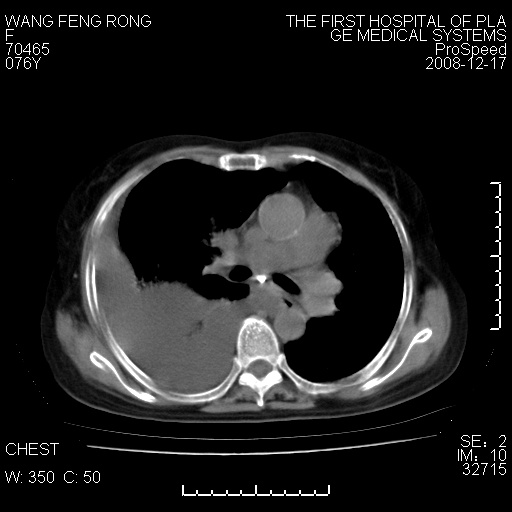

右肺大部实变,其内可见支气管影,但分支减少,宽窄不均,走行僵直,同侧胸腔大量积液;纵隔内见多发淋巴结影,但淋巴结大部有钙化;主动脉壁钙化;临床上病人咳嗽、消瘦。所以我考虑:1、结核(依据:右下肺实变,纵隔内淋巴结符合结核表现,同侧并发胸膜炎表现);2、支气管肺泡癌(依据:实变的肺组织内支气管分支减少,宽窄不均,走行僵直,没有把它放在第一诊断是因为没有看到明显肿大的淋巴结);3、动脉硬化(主动脉壁钙化就支持这个诊断)。

1)考虑两肺炎症感染;不排除肺泡癌可能。2)两肺间质纤维化。3)右侧胸腔积液。

病理结果,肺泡癌